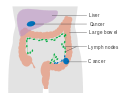

| Diagram of the lower gastrointestinal tract | |

Colorectal cancer (CRC), also known as bowel cancer, is the development of cancer from the colon or rectum (parts of the large intestine).[1] It is due to the abnormal growth of cells that have the ability to invade or spread to other parts of the body.[2] Signs and symptoms may include blood in the stool, a change in bowel movements, weight loss, and feeling tired all the time.[3]

Treatments used for colorectal cancer may include some combination of surgery, radiation therapy, chemotherapy and targeted therapy.[1] Cancers that are confined within the wall of the colon may be curable with surgery while cancer that has spread widely are usually not curable, with management being directed towards improving quality of life and symptoms.[1] Five year survival rates in the United States are around 65%.[9] This, however, depends on how advanced the cancer is, whether or not all the cancer can be removed with surgery, and the person's overall health.[3] Globally, colorectal cancer is the third most common type of cancer making up about 10% of all cases.[10] In 2012, there were 1.4 million new cases and 694,000 deaths from the disease.[10] It is more common in developed countries, where more than 65% of cases are found.[4] It is less common in women than men.[4]